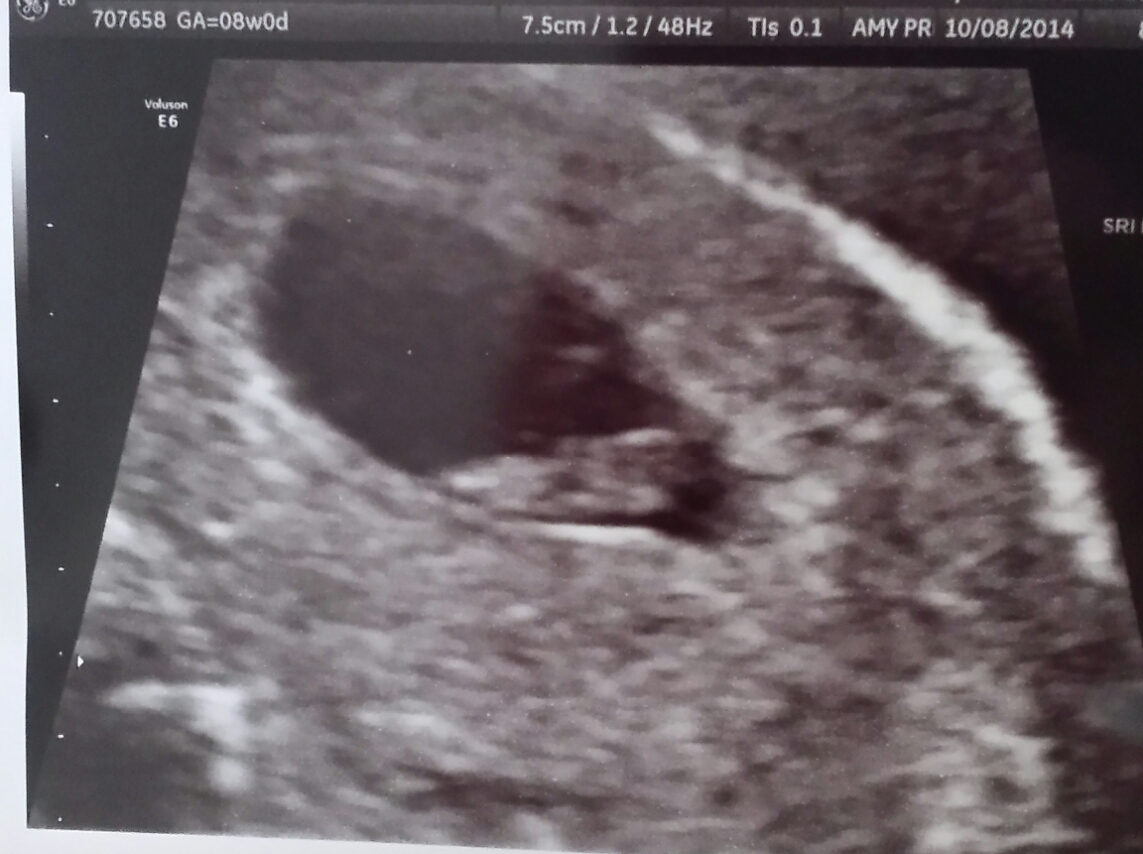

Hey ladies! Just want to AW my newest addition. Went to the doctors this morning and it took forever, but got to see LO via abdominal ultrasound. Measuring 7w5d and a heartbeat of 150bpm. EDD is still May 20th, 2015. I cannot believe it. He or She is healthy and wiggling around. My DH and I are so excited! Thankfully, there was only one in there, I don't think I could handle twins like some of you other mama's. Thanks for stopping by and looking at my blob